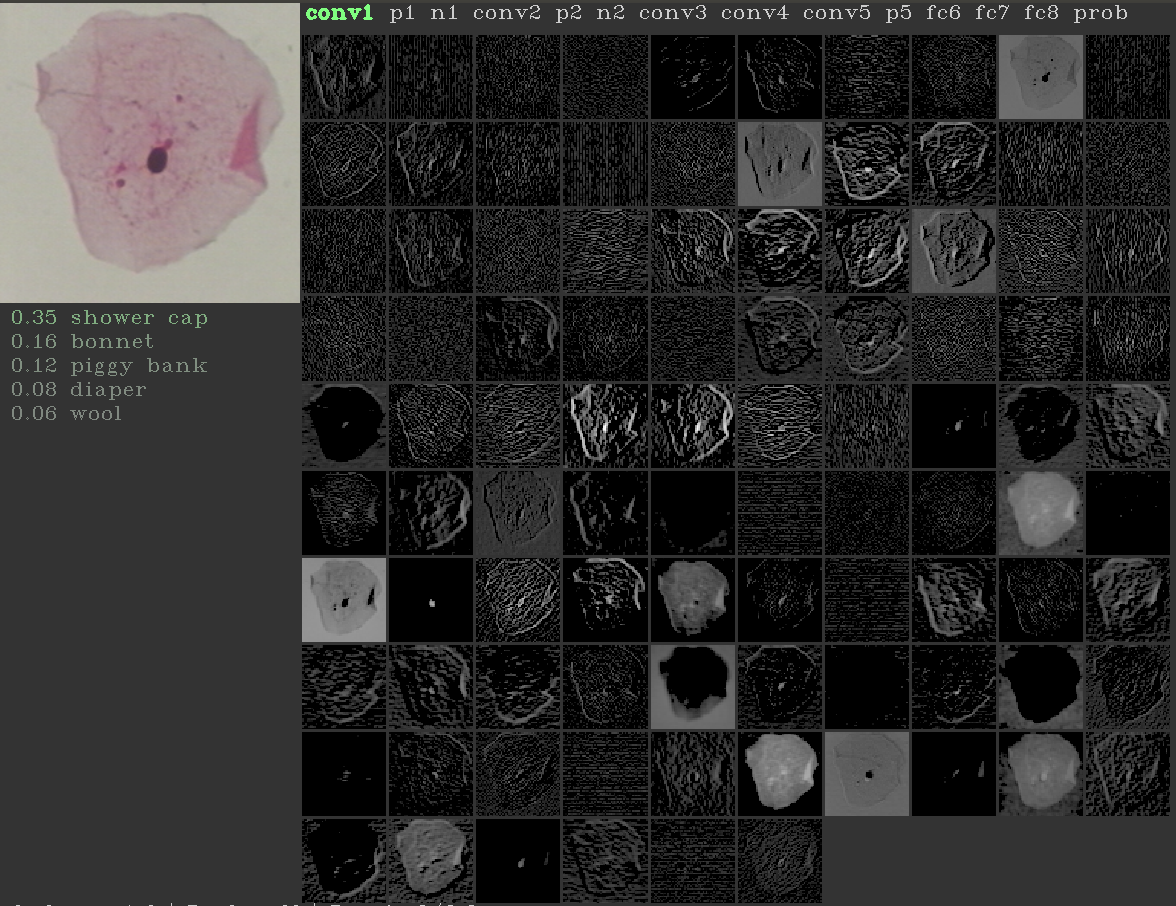

It is shown in literature that the lower level convolutional layers learn the low-level primitive features such as gradients, texture etc., and the deeper layers, learn the high-level data specific semantic features [21]. Considering the hypothesis that semantic features may not be important for cell classification, we explore for classification, the outputs from the filters learned by Alexnet [16] at last (conv5), intermediate (conv3) and first (conv1) convolutional layers followed by two fully connected layers which we retrain, one consisting of 256 neurons and the last layer consisting of number of neurons equal to number of classes. We refer to these new transfer-learning based networks in the rest of the paper as conv5T (Figure 4), conv3T (Figure 5) and conv1T (Figure 6).

Figure 6: conv1T: features from first convolutional layer of Alexnet

Activation map from different convolutional layers of Alexnet for an example image are shown in Figure 10. It can be seen that the activation map from the first convolutional layer learns the prominant texture features from the images as opposed to the third and fifth convolutional layers. This observation supports the hypothesis that for cell images, as the depth of the network increases, the high-level features do not seem informative. This also supports our motivation to select Alexnet consisting of smaller number of layers. We provide the average training, validation and testing accuracies for the 7-class classification, over 5 random trials for different architectures in Figure 9. The constant increase in accuracies from conv5T to conv1T shows that the cell classification problem performs better with low-level features rather than those at the deeper levels. We believe this is an interesting and important insight, as typical deep learning approaches only consider the last layer features for classification.

Refer to caption

(a)

(b)

(c)

Figure 10: Activation maps: Left to Right: Conv1, Conv3 and Conv5 activation maps for Normal superficial cell images.